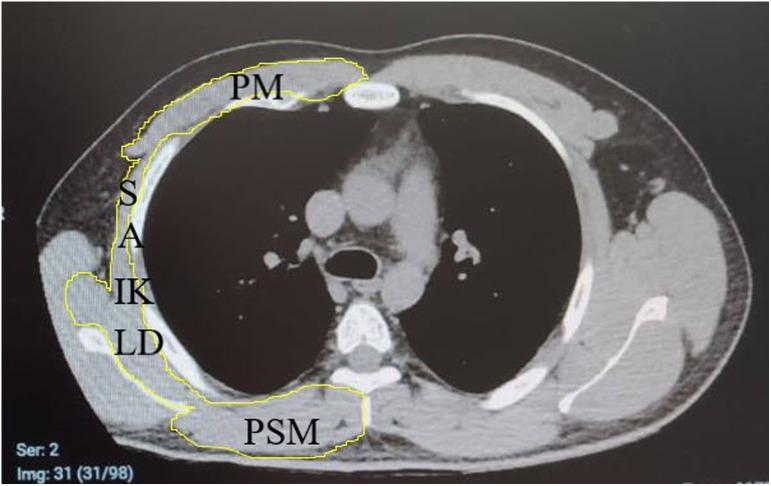

MATERIAL AND METHODS

Two hundred twenty-three subjects (patient group = 161 and control = 62) who presented to our coronavirus disease 2019 outpatient clinic between May 2020 and September 2020 were included in the study. The medication, oxygen, and intubation requirements of the patients and their disease duration and hospital stay were also recorded. At the T4 level, thoracic and back (pectoralis, intercostalis, paraspinals, serratus, and latissimus dorsi) muscles and at the T12 level erector spinae muscles were measured in terms of area (cm2 ).

材料与方法

本研究纳入了2020年5月至2020年9月期间到我院2019冠状病毒病门诊就诊的223名受试者(患者组=161名,对照组=62名)。记录患者的用药、吸氧和插管需求以及他们的病程和住院时间。在T4水平测量胸部和背部(胸大肌、肋间肌、椎旁肌、锯肌和背阔肌)肌肉,在T12水平测量竖脊肌的面积(cm²)。